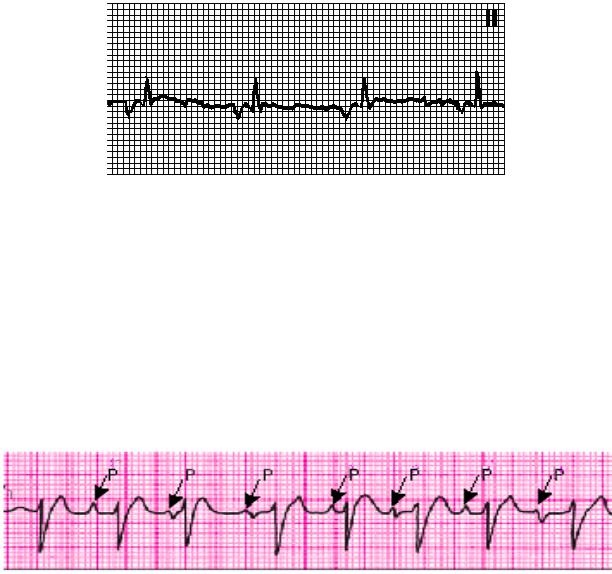

автоматизм. Коронарный синус расположен внизу правого предсердия вблизи АВ-узла в месте впадения в правое предсердие сердечной вены. Близкое расположение от АВ-узла ведёт к более быстрому попаданию импульса возбуждения в желудочки. Признаками ритма коронарного синуса являются отрицательные зубцы Р в отведениях II, III и aVF и продолжительность интервала PQ менее 0,12 с (рис. 3.5).

Рис. 3.5. ЭКГ во II отведении при ритме коронарного синуса (PQ=0,10 с)

Эктопический ритм может возникать не в одной точке предсердий, а попеременно в разных участках от синусового узла до АВ-соединения. Такое нарушение ритма называется миграцией водителя ритма. Признаками миграции водителя ритма по предсердиям (рис. 3.6) являются:

1)аритмия;

2)непостоянство продолжительности интервала PQ;

3)изменяющиеся в одном и том же отведении форма и/или полярность

зубца Р.

Рис. 3.6. Миграция водителя ритма (пояснения в тексте)